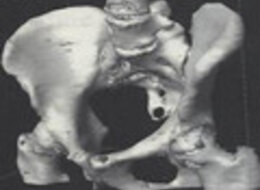

Ein Volumen CT bringt eine Verkürzung der Untersuchungszeit bei besserer Bildqualität.